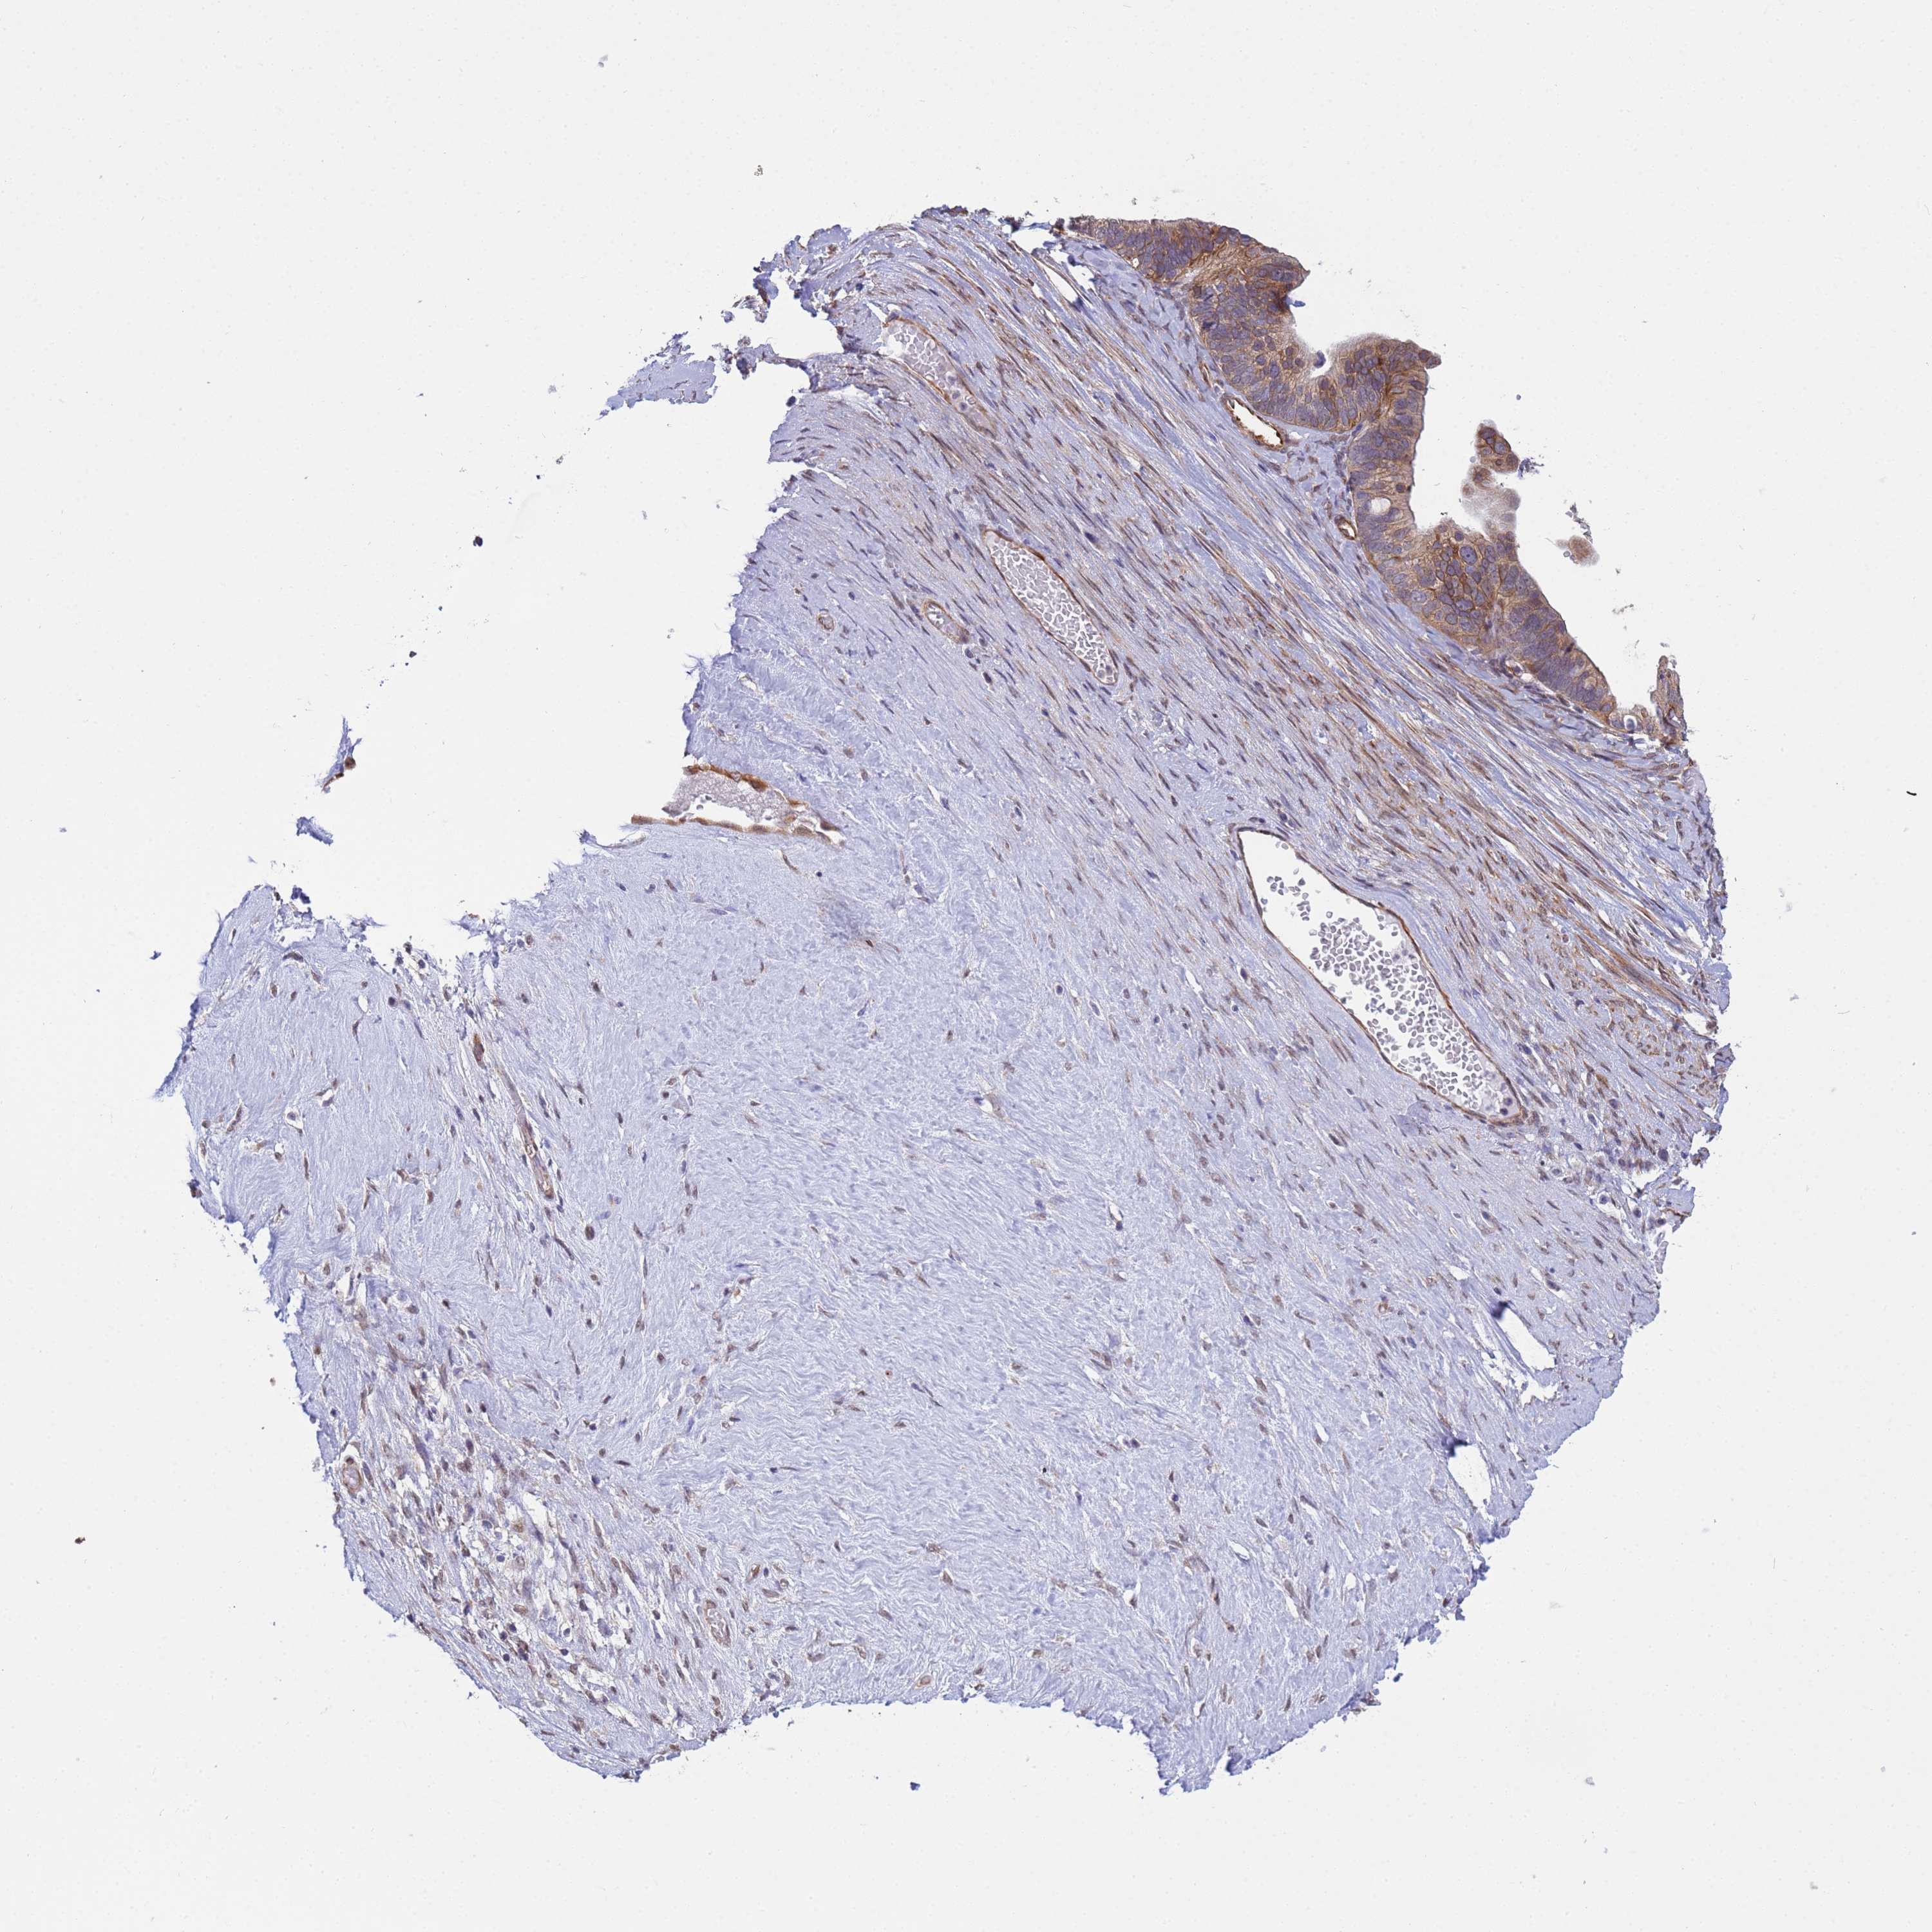

OVARIAN CANCER - Protein expressioni

A mouse-over function shows sample information and annotation data. Click on an image to view it in a full screen mode. Samples can be filtered based on level of antibody staining by selecting one or several of the following categories: high, medium, low and not detected. The assay and annotation is described here.

Note that samples used for immunohistochemistry by the Human Protein Atlas do not correspond to samples in the TCGA dataset.

Antibody stainingi

Antibody staining in the annotated cell types in the current human tissue is reported as not detected, low, medium, or high, based on conventional immunohistochemistry profiling in selected tissues. This score is based on the combination of the staining intensity and fraction of stained cells.

Each image is clickable and will lead to virtual microscopy that enables deeper exploration of all samples and also displays staining intensity scores, fraction scores and subcellular localization as well as patient and tissue information for each sample.

Antibody HPA036348

Antibody HPA036349

Antibody CAB002422

Antibody CAB005258

Cystadenocarcinoma, serous, NOS

Carcinoma, NOS

Cystadenocarcinoma, mucinous, NOS

Carcinoma, endometroid